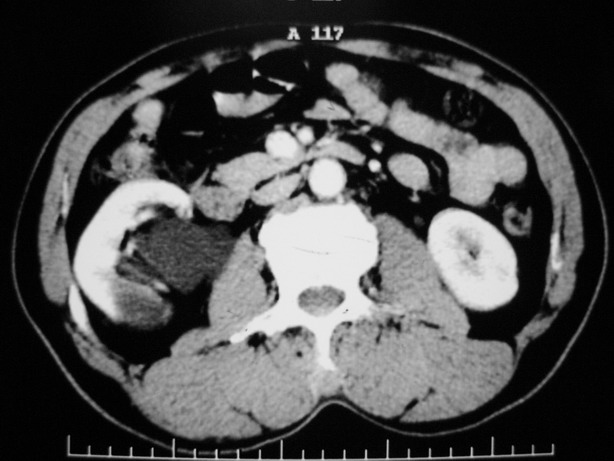

标题: CT10772:男性,48,右肾盂旁多囊性占位!

男性,48,体检发现,平时无症状。

收集期:

延迟期造影剂没有进入囊性病灶内考虑多发性肾囊肿,包括一个盂旁囊肿。

肾盂旁多囊性占位,有实性成分,增强有轻度强化,收集期病变内无造影剂显影。诊断肾盂旁囊肿,有实性成分无法解释,查书后诊断为:多房性囊性肾瘤!!不知大家同意否?????????对本病知道不多,望大家不吝赐教!!

囊间间隔强化与肾实质相仿,还是支持多发囊肿,定期复查